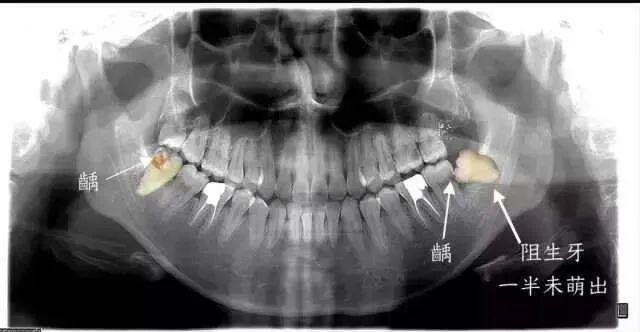

从下图可见,这些是被拔去的相对完整智齿,而更多的智齿其实已经在拔牙过程中四分五裂。即便如此,这些幸存下来的智齿,或多或少也已经出现了各种龋损和破坏。

虽说大多数被拔的智齿,都或多或少会引起、或曾经引起疼痛。

但痛或不痛并非医生确定,智齿要不要拔除的根本原因。